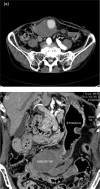

An 85-year-old man complaining of vague abdominal discomfort was admitted to our hospital. A pulsatile 8 × 7-cm mass in the right upper abdomen was noticed on clinical examination. Computed tomography of the abdomen showed a huge arterial aneurysm in the right gastroepiploic artery, and the left gastroepiploic artery was meandering and expanding. An image diagnosis of gastroepiploic arterial aneurysm (GEAA) was made. Because of the huge size of the aneurysm and the predicted high risk of perforation, surgical intervention was planned. The aneurysm was identified in the greater curve and was found to adhere firmly to the transverse colon. Partial resection of the stomach, aneurysmectomy and partial resection of the transverse colon were performed. Clinically, splanchnic arterial aneurysms are rare. Among them, GEAA is especially rare. We report a rare case of a huge GEAA that was treated successfully by surgery.